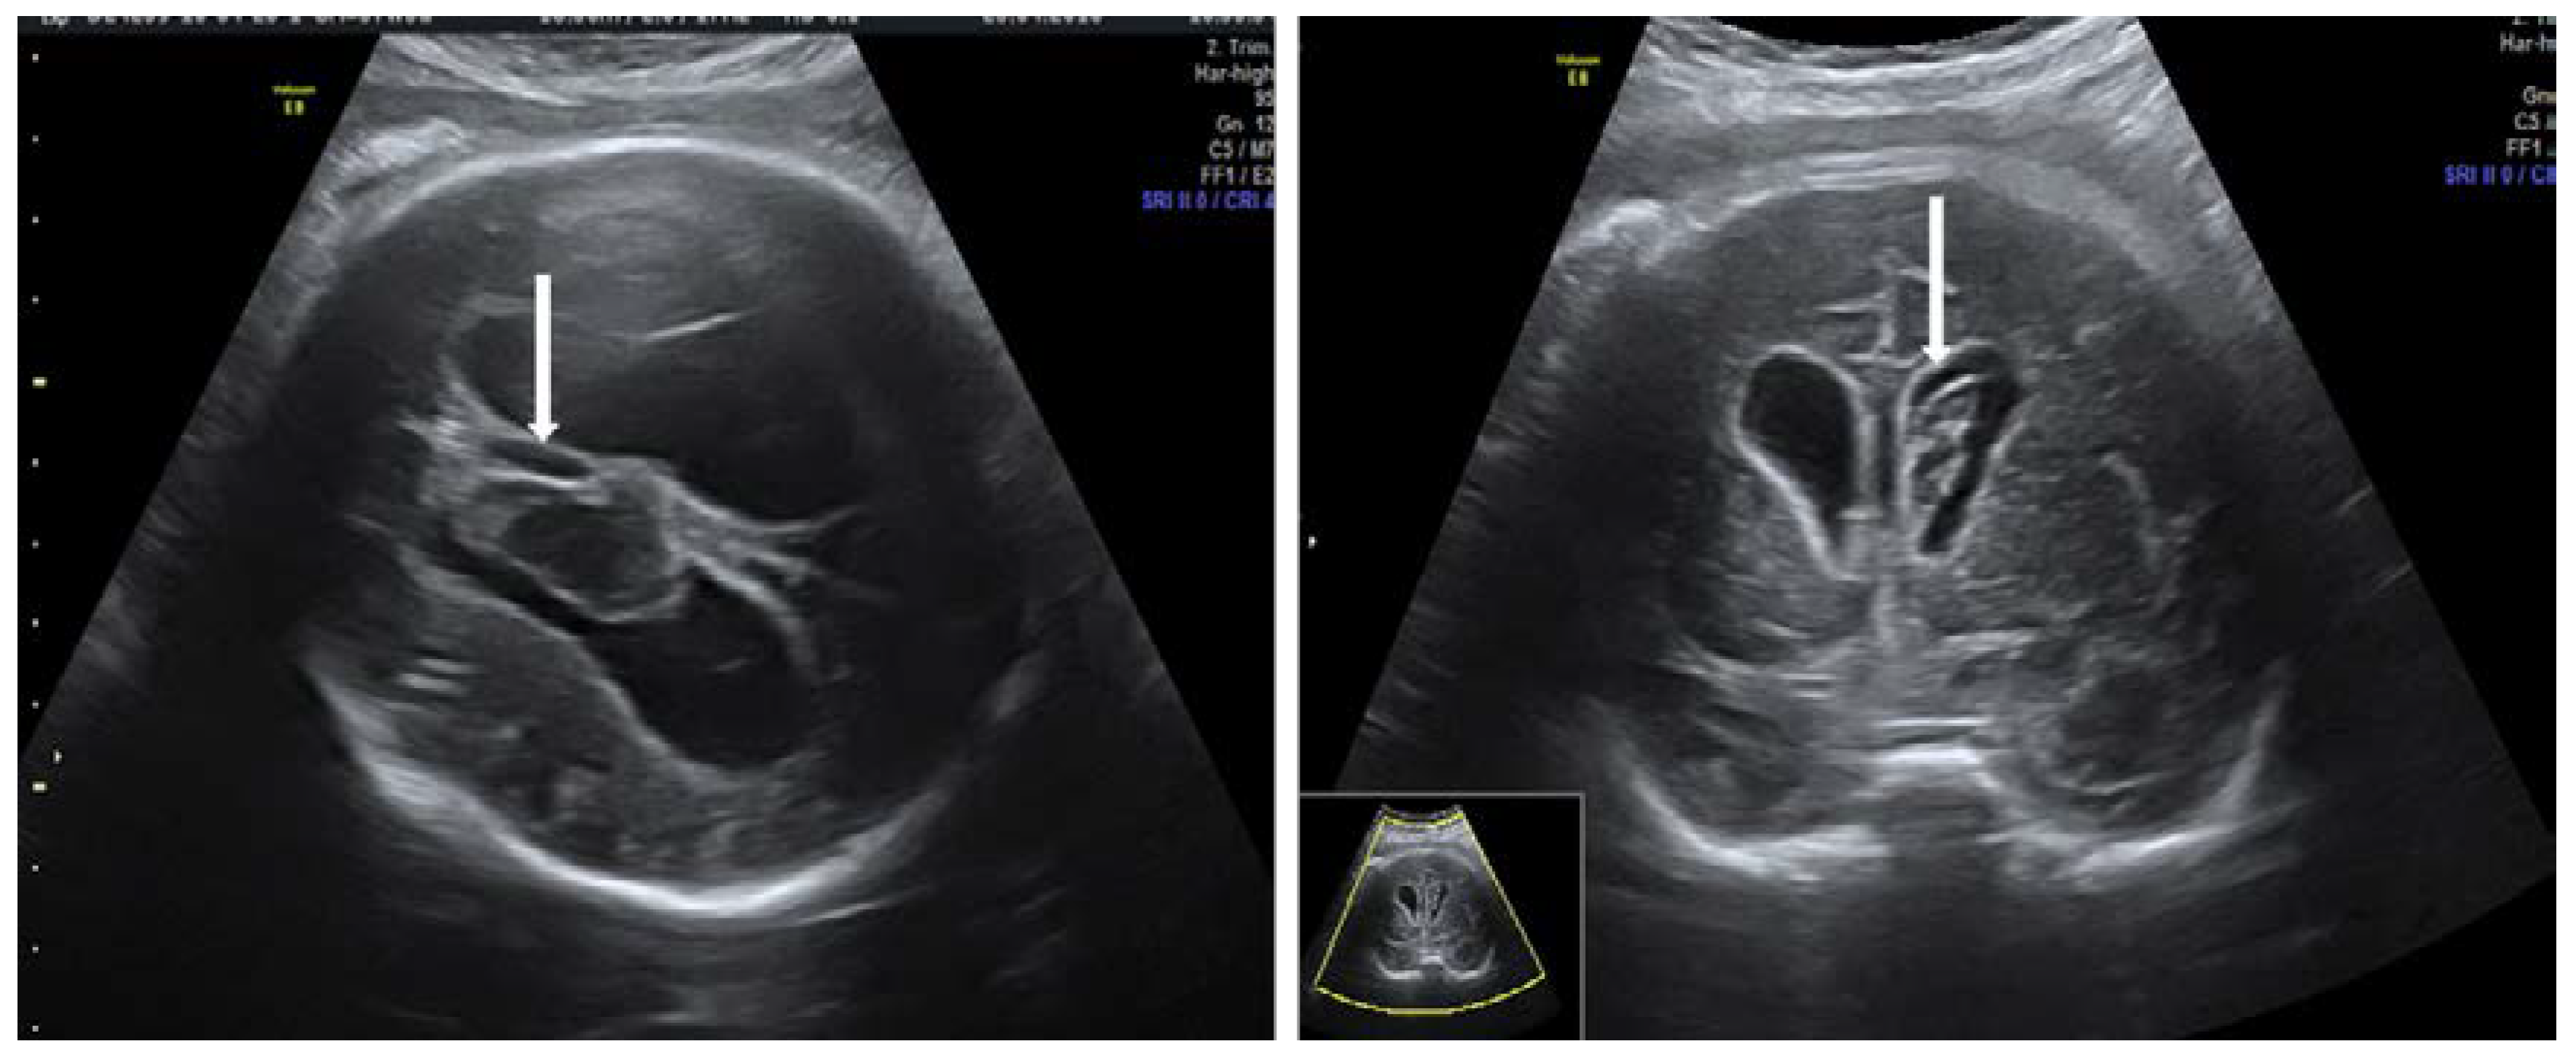

3.3. Primary Autoimmune Thrombocytopenia—ITP Antibodies

- Wainwright, B.; Bhan, R.; Trad, C.; Cohen, R.; Saxena, A.; Buyon, J.; Izmirly, P. Autoimmune-mediated congenital heart block. Best Pract. Res. Clin. Obstet. Gynaecol. 2019, 64, 41–51. [Google Scholar] [CrossRef]

- Brito-Zerón, P.; Izmirly, P.M.; Ramos-Casals, M.; Buyon, J.P.; Khamashta, M. The clinical spectrum of autoimmune congenital heart block. Nat. Rev. Rheumatol. 2015, 11, 301–312. [Google Scholar] [CrossRef] [PubMed]

- Eliasson, H.; Sonesson, S.E.; Sharland, G.; Granath, F.; Simpson, J.M.; Carvalho, J.S.; Jicinska, H.; Tomek, V.; Dangel, J.; Zielinsky, P.; et al. Isolated atrioventricular block in the fetus: A retrospective, multinational, multicenter study of 175 patients. Circulation 2011, 124, 1919–1926. [Google Scholar] [CrossRef]